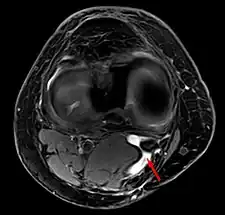

Baker's cyst on axial MRI with communicating channel between the semimembranosus muscle and the medial head of the gastrocnemius muscle.